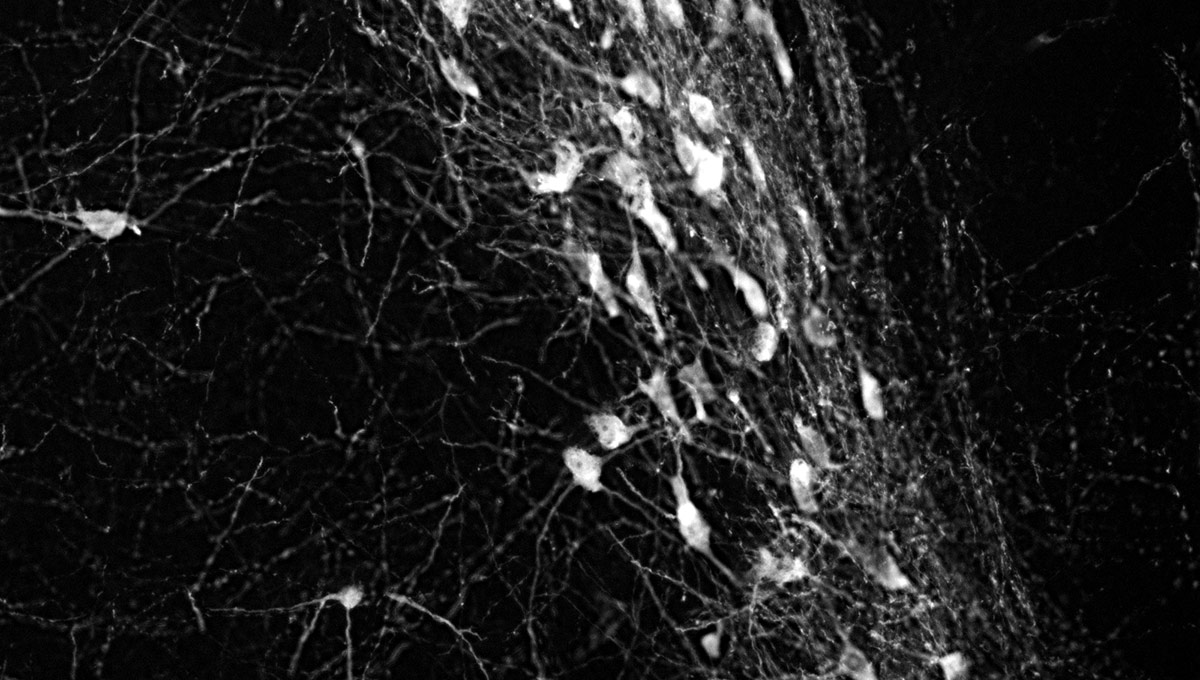

The green microscope image featured above is from Matthew Holahan’s experiments and shows the accumulation of a protein called alpha-synuclein in a mouse brain; the bright spots show alpha-synuclein aggregating into clumps of spaghetti-like filaments that, researchers believe, lead to decreases in dopamine and Parkinson’s symptoms such as slow movements, tremors and rigidity. The red image shows A-syn-1, the aptamer Holahan and Maria DeRosa designed to target the protein. The yellow image shows the successful co-localization of A-syn-1 and alpha-synuclein, which has the potential to help stop Parkinson’s disease. The black-and-white images, in order of appearance from top to bottom, show: dopaminergic neurons in the substania nigra, part of the midbrain where Parkinson’s pathology occurs and affects motor function — dopaminergic neurons are the main source of dopamine in the brain; the motor cortex, where Holahan and DeRosa’s research is focused; and what neurodegeneration looks under a microscope.